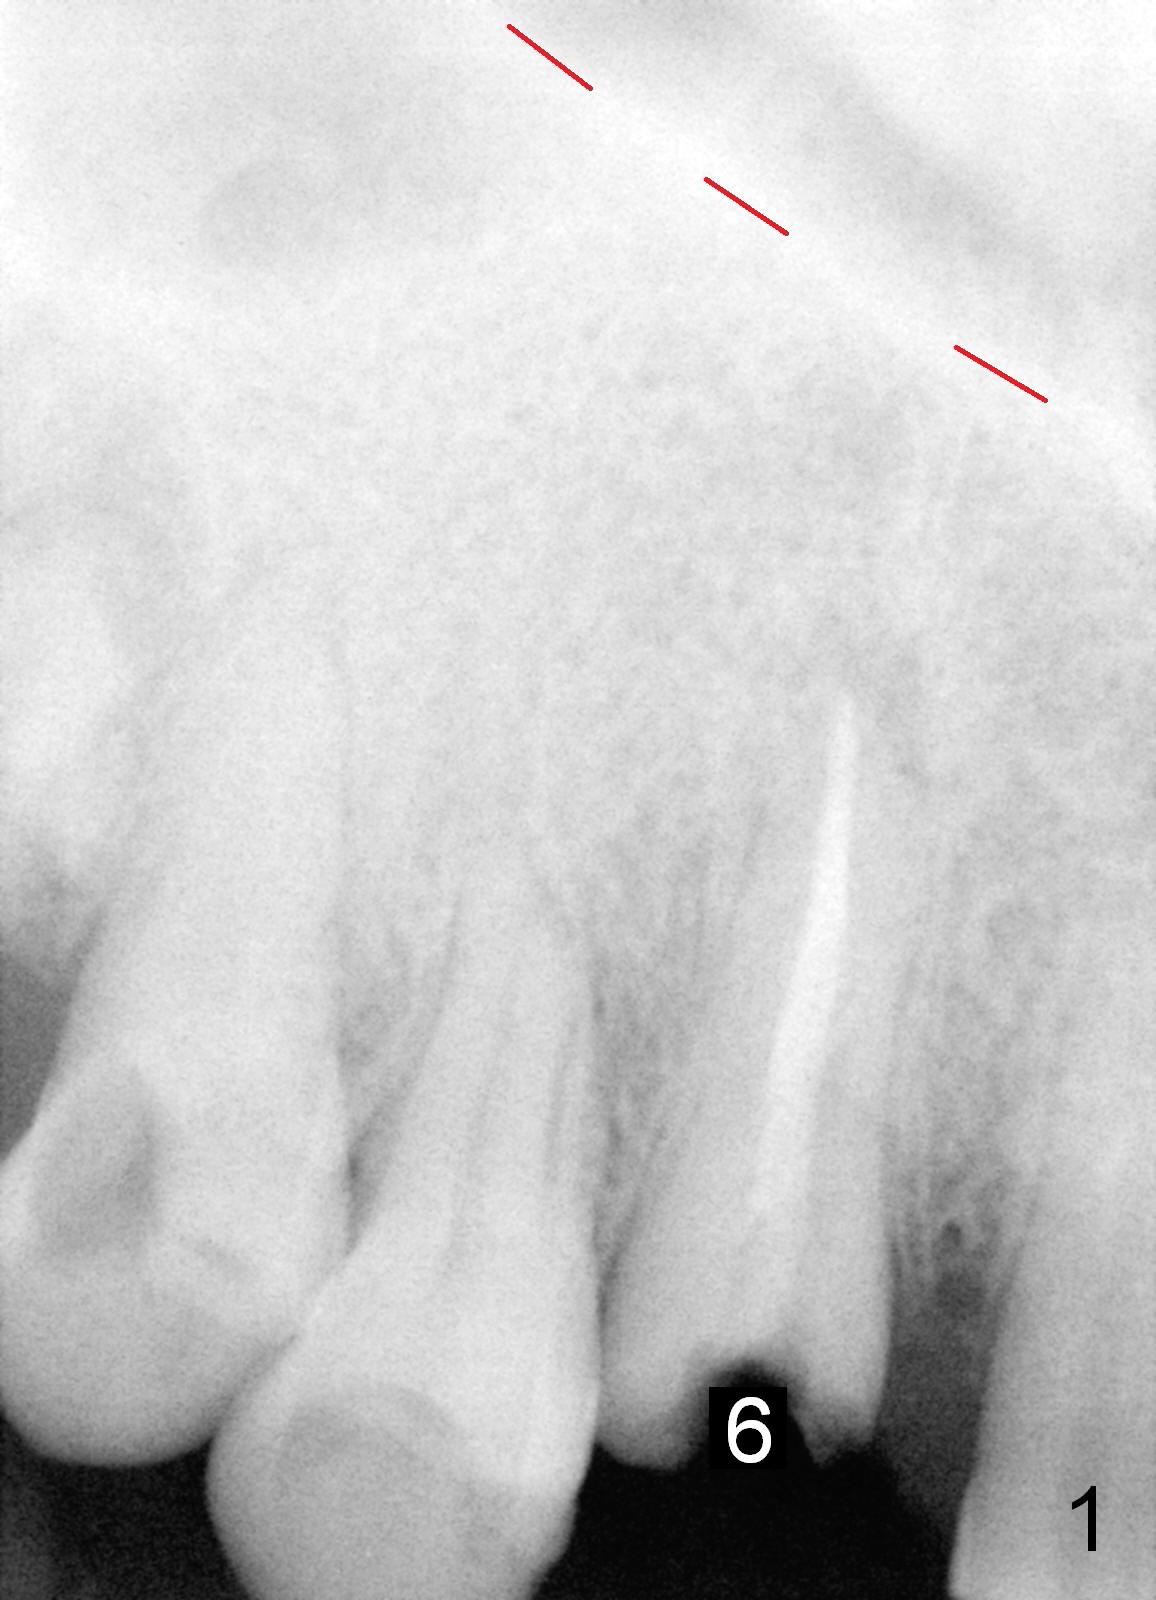

Recently tissue-level implants have been used successfully for upper canines (1 , 2). The prominent feature of the implants is the length (20 mm) with primary stability. Although the longest bone-level implant is 14 mm, the advantage of the latter is its temporary abutment. With it, the tissue forms beautifully with a central incisor. A 43-year-old man fractures #6 (Fig.1: red dashed line: nasal floor). Although a 5x20 mm tissue-level implant is a good option (Fig.2), a 5x14 mm bone-level implant should be able to achieve primary stability (Fig.3). Anyway, either implant should be placed as palatal as possible, particularly for bone-level one, because the temporary abutment should exit palatal to the incisal edge. If position or angulation of the bone-level implant is not ideal, an angled abutment will be used. Check occlusion carefully before and after immediate provisional cementation. Is the 5x14 mm implant long enough?